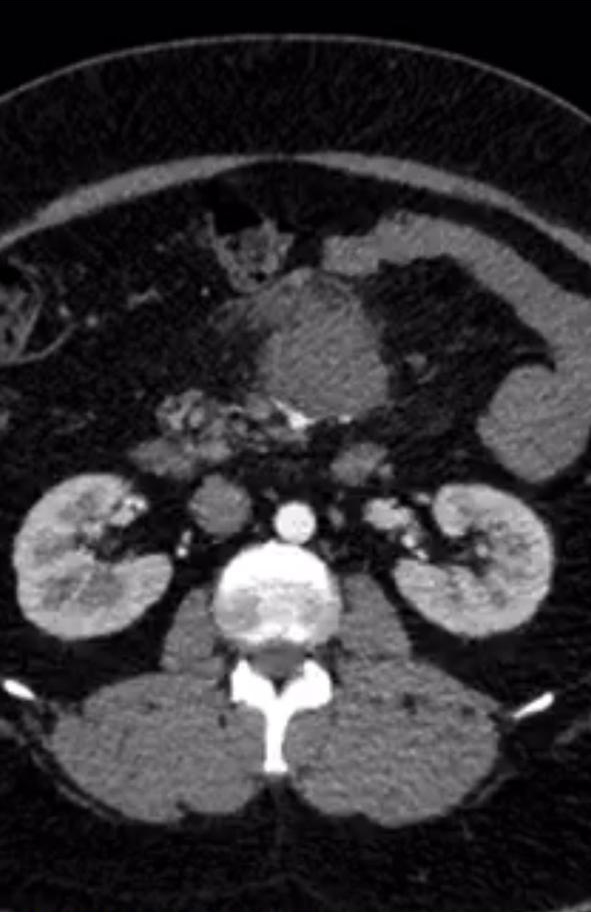

A 45 year old gentleman presented to us with vague abdominal pain. CT showed a large 6-7 cm tumor in the central mesentery sitting on important intestinal blood vessels. A CT guided biopsy proved it to be a sarcoma. The patient was obese but tumor seemed amenable for a laparoscopic surgery wherein the tumor was removed. Patient was discharged by 5th postoperative day.